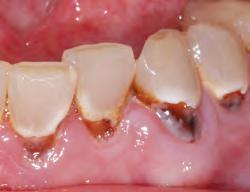

• Stains carious and demineralized dentin

• Provides precise, mess-free delivery

• Available in dark green for working near pulp

Sable Seek caries indicator contains FD&C dyes, and Seek caries indicator contains D&C dyes in a glycol base. Both are used to stain carious and demineralized dentin.

Seek and Sable Seek caries indicators stain carious and demineralized dentin and can be very useful for difficult-to-see areas, for example; undercuts of preparations, dark dentin, areas along the DE junction, etc. Green Sable Seek caries indicator helps visualization of decay in deep caries cases to help avoid pulp exposures.

PROCEDURE

dentin) with slow-speed round bur or excavator. To control overexcavating near the pulp, remove final portion of caries with hand excavator.